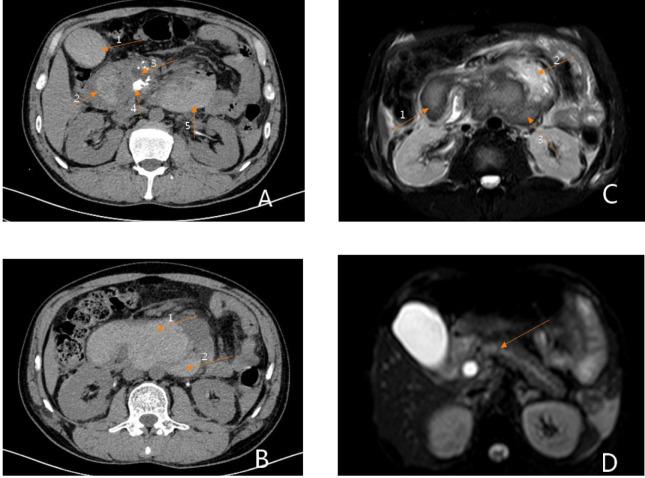

We here present the case of 40-year-old male who presented with abdominal pain and vomiting for two days and 10 h, respectively. He had a history of chronic pancreatitis and pseudocysts. The symptoms of abdominal pain worsened in the second day. Laboratory tests showed a progressive decrease in hemoglobin. Then, emergency pancreatoduodenectomy was performed. Intraoperative exploration found a small blood clot in the abdominal cavity and a hematoma that had formed in the intestinal cavity and retroperitoneum.

This case showed that pseudocysts of the pancreas can rupture under certain circumstances, leading to intraperitoneal bleeding and hematoma formation, which can endanger the life of the patient. And surgical treatment can be the first choice for hemorrhagic pseudocysts.